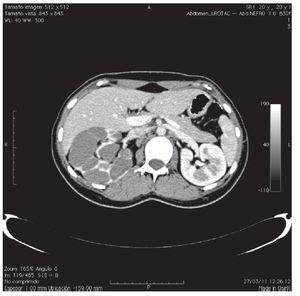

Paciente femenino de 20 años de edad, antecedente de extrofia vesical con cierre espontáneo. A la exploración física, se encuentra la presencia de duplicación de genitales internos y externos (clítoris, vaginas, útero), así como falta de fusión de la pelvis ósea (Figura 1). Paciente acudió al servicio de urología, por la presencia de dolor en el flanco derecho y una masa palpable. Se le realizó tomografía, donde se evidenció una bolsa hidronefrótica derecha y la presencia de dos vejigas con uretras independientes y un útero doble (Figuras 2 y 3). En la resonancia magnética, se pudieron identificar dos vejigas no comunicantes con interface entre las dos (Figuras 4 y 5). Se envió a genética reportándose cariotipo de 46XX. Se realizó cistografía, donde se evidenció la presencia de duplicación vesical completa y presencia de reflujo vesicoureteral derecho grado IV. Se realizó cistoscopia con lente pediátrico de 30 grados, observando en la uretra derecha hemivejiga con meato ureteral ortotópico dilatado, sin visualizarse el izquierdo, ni conexión a hemivejiga izquierda. Se realizó el mismo procedimiento en la uretra izquierda, visualizando uréter ortotópico y eyaculante. Se diagnosticó doble sistema genitourinario completo, con reflujo vesicoureteral grado IV y exclusión renal derecha. Se programó para nefroureterocistectomía derecha.

Figura 2.La tomografía axial computada, muestra riñón derecho hidronefrótico.